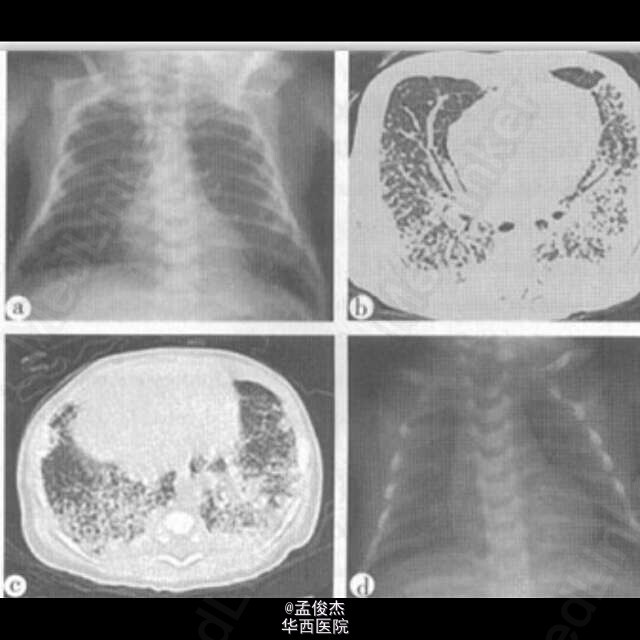

资料:患儿女,13 d。咳嗽、吐沫4 d,无发热。影像学表现:x线胸片显示两肺弥漫分布网织结节影,中内带较外带著明,两肺过度充气;上纵隔小儿胸腺不明显(图a)。胸部CT显示两肺广泛分布小结节及网格影,背侧较前侧著明,胸膜下可见结节及融合斑片影,支气管血管束增粗(图b、c)。红霉素治疗14 d后X线胸片显示肺内病变明显吸收好转,两肺清晰,上纵隔小儿胸腺较前著明(图d)。影像学诊断:两肺间质浸润伴少许实质改变,衣原体感染可能。 临床诊断:肺炎衣原体感染。